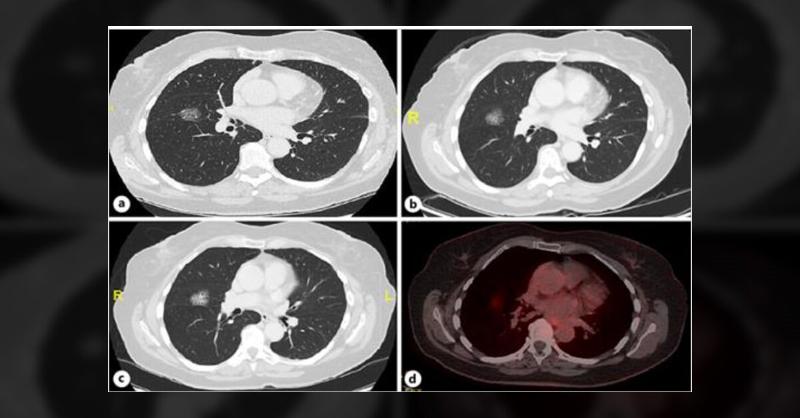

A Case Study on Primary Pulmonary MALT Lymphoma Treated with Radiation Therapy

Primary pulmonary lymphomas (PPLs), excluding diffuse large B-cell lymphomas, are rare neoplastic disorders defined by pulmonary lesions without evidence of lymphoma elsewhere. Accounting for 0.5–1% of pulmonary malignancies, 90% of PPLs are mucosa-associated lymphoid tissue lymphomas (MALTomas), prevalent in the 6th and 7th decades, often linked t